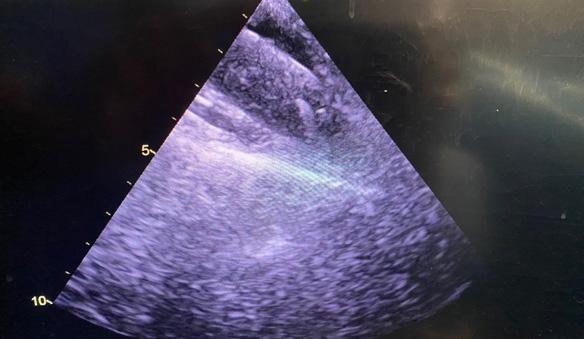

Minitoracotomia dreaptă

Pacientul este plasat în decubit dorsal cu umărul drept ușor ridicat; este anestezi at și intubat cu sondă dublu lumen care să permită ventilația selectivă pulmonară. Se introduce o sondă de ecocardiografie tran sesofagiană (ETE) cu ajutorul căreia se confirmă diagnosticul preoperator și me canismul patologiei mitrale, se ghidează canularea periferică pentru circulație ex tracorporală (CEC) și se evaluează funcția cadiacă și calitatea gestului asupra VMi. Pacientul este rotat 30 grade către stânga, efectuându-se o toracotomie antero-la terală de 5-7 cm în al IV-lea spațiu inter costal. Rotirea pacientului către stânga nu este obligatorie, multe centre renunțând la această abordare, din cauză că inima se îndepărtează de toracele drept. În schimb, este important ca brațul drept să fie flectat la 120 grade și în ușoară abducție, pentru a se îndepărta de viitoarea incizie (Fig.1,2).

zitive de etanșeizare vasculară tip Proglide. ETE confirmă prezența ghidului în lumenul aortei descendente toracice (Fig.6), preve nind cea mai de temut complicație a canu lării periferice: disecția retrogradă de aortă.

Abia după ce se confirmă localizarea ghidului, se avansează canula arterială femurală. După canularea arterială se continuă cu cea venoasă. Indiferent dacă se utilizează o canulă “single-stage” sau “dual-stage”, ghidul trebuie avansat și ve rificat în atriul drept (AD) până la nivelul venei cave superioare (VCS) (Fig.7).

Se avansează apoi cu canula venoasă; în cazul canulării VCI se verifică ecogra fic și tactil (dacă se poate) prezența canu lei la joncțiunea VCI cu AD (Fig.8).

În chirurgia mitrală și/sau tricuspidi ană minim invazivă standard, canula ve noasă femurală este plasată imediat caudal de joncțiunea cavoatrială inferioară, iar ca nula jugulară este introdusă percutanat în VCS de către medicul anestezist (Fig.9, 1). Expunerea cordului și a valvei mitrale. Protecție miocardică.

După atingerea ACT-ului standard, mai mare de 480 secunde, se pornește CEC. Se preferă abordarea prin care se golește mai întâi cordul, urmată de inci zia pericardului la 2-3 cm superior de nervul frenic drept și suspensia acestuia, pentru a nu leza cordul în cursul acestor manevre (Fig.10).

Disecția completă cu electrocauterul a șanțului interatrial este un aspect critic în expunerea VMi. Aceasta se efectuează până la nivelul fossei ovalis, aducând chi rurgul foarte aproape de VMi, chiar și în situații anatomice dificile (Fig.11).